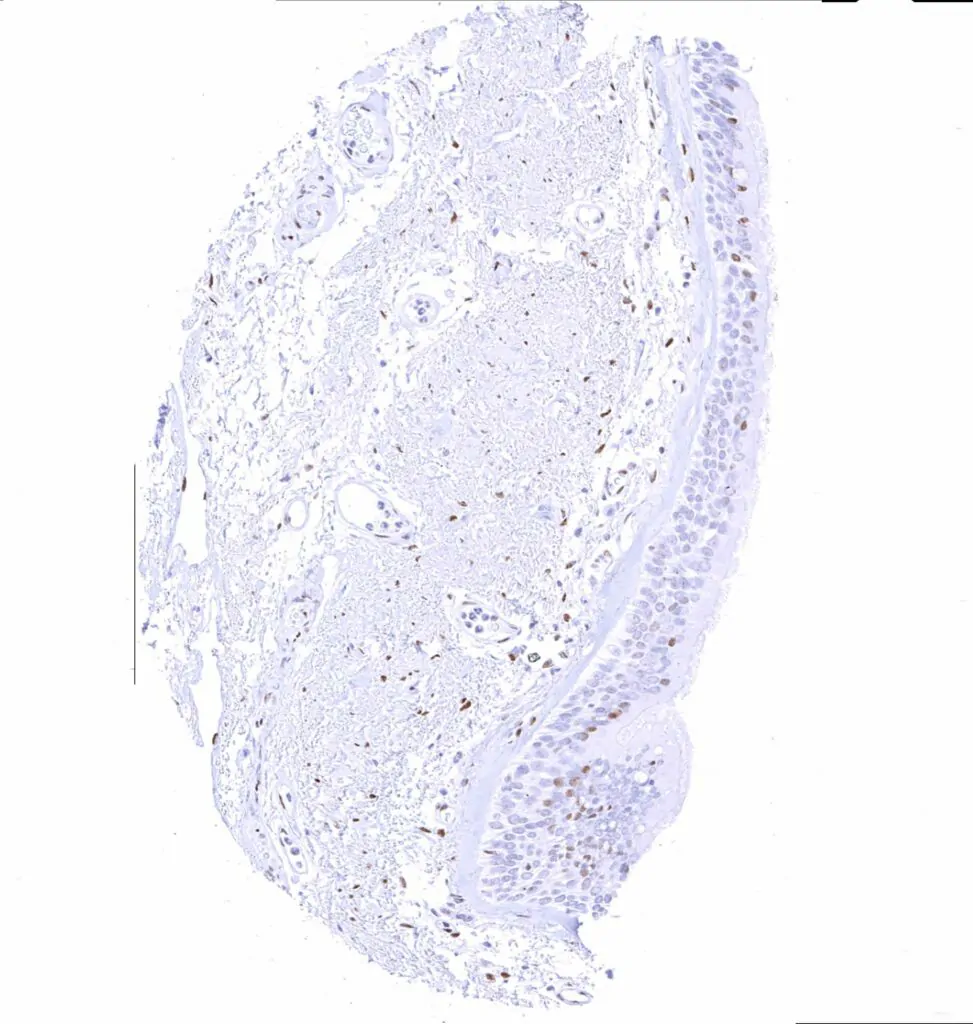

Uterus, ectocervix – Moderate TLE1 staining of squamous epithelial cells, predominantly of the suprabasal cell layers